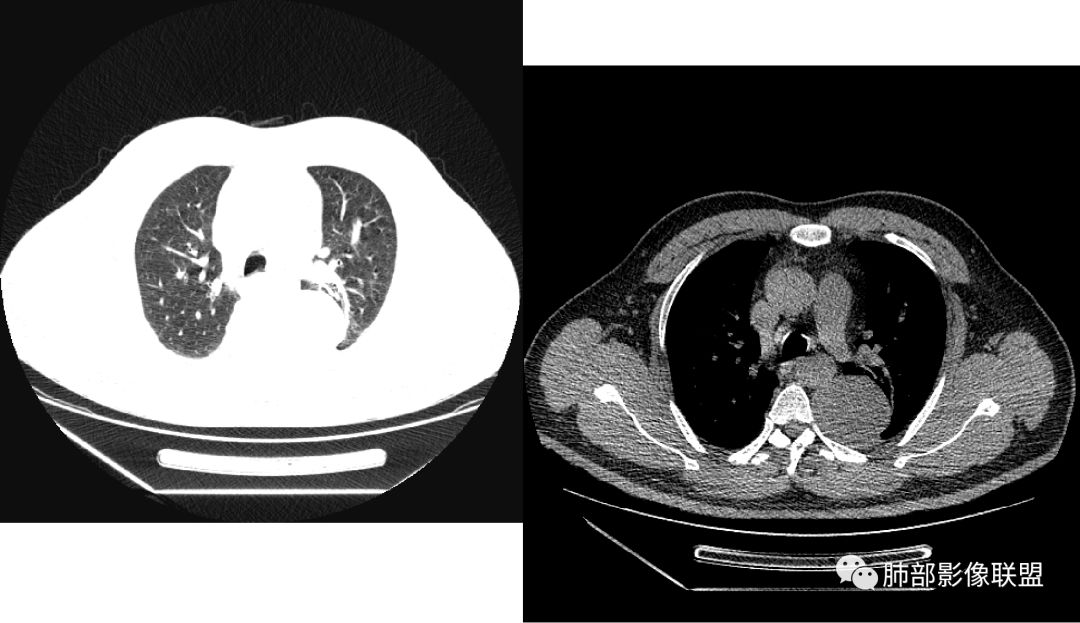

曹志勇:右肺尖后段类圆形病灶,边界清边,缘锐利,宽基底与胸膜相连,环形强化,内似见蛇纹血管征,考虑胸膜孤立性纤维瘤,右肺外底段病灶,考虑炎性可能大

左肺下叶脊柱旁病灶,可见胸膜尾征,均匀强化,临近椎间孔未见扩大,考虑孤立纤维瘤,鉴别诊断神经源性肿瘤,右肺下叶病灶边缘平直,明显均匀强化,边缘清楚,考虑机化性肺炎。

张帅:患者中年男性,咳嗽 咳痰3月,痰为白色粘痰,左上肺病灶,边缘光滑,周围未见毛刺 分叶,肺组织受挤压,与胸膜关系密切,部分层面与胸膜脂肪间隙消失,有胸膜尾征,病灶定位于胸膜,病灶增强可见强化,边缘可见增强血管,内可见低密度区,考虑 孤立胸膜纤维瘤?神经鞘瘤?右肺下叶外基底段病灶,病灶与胸膜有牵拉,病灶边缘光滑,平直 u型征,未见明显毛刺,增强病灶内可见增强血管影,边缘低密度,考虑病灶内存在痰栓。右下肺病灶考虑良性炎症性病灶,ABPA?

可芸:定位:肺外病变,胸椎旁肿块,边缘清晰光整,可见胸膜尾征无支气管进入,肺组织受压。轻度强化,密度稍不均匀,未见肺动脉供血,考虑良性肿瘤,神经源性,孤立性纤维瘤?右肺下叶病灶,轻度强化,血管显影,边缘平直、凹陷,炎性病变。

王秀仙:左侧后纵膈占位,位于胸膜下,胸膜被顶起,有胸膜尾征,密度均匀,轻度强化,内可见斑点钙化。周围肺组织结构推移。右肺下叶可见片状影,沿支气管走行,边缘平直收缩,强化明显,胸膜有牵拉。二元论,考虑1左侧后纵膈神经鞘瘤。鉴别SFT.2右肺下叶炎性肉芽肿。

心灵鸡汤:先定位再定性,左侧胸椎旁沟见一团状软组织影,边清,密度均,推挤周围组织,增强轻度强化,考虑为良性肿瘤,来源于后纵隔神经源性的肿瘤,神经鞘瘤可能,鉴别孤立性纤维瘤,孤立性真菌类。左肺下叶外基底段斑片影,倾向机化性肺炎或慢性炎症可能。请老师指点

等待戈多:左侧脊柱旁软组织肿块,边界清楚,肺外胸膜来源,肺组织受压,增强有强化,考虑SFT 鉴别神经源性肿瘤;右肺下叶斑片影,明显强化,边缘平直 考虑炎性病灶。

薏米:左下近脊柱旁可见一结节状密度增高影,肺外,边界清,边缘规整,无分叶,无毛刺,无棘突,宽基底与胸膜相连,不均匀轻度强化,考虑为良性病变,神经源性可能性大,为神经鞘瘤,鉴别孤立性神经纤维瘤,神经节瘤,右肺片装密度增高影,考虑为炎症可能性大

崇军:左侧胸椎旁肿块,边缘清晰光整,有胸膜尾征,冠状位为D字征,定位肺外。轻度强化,密度稍不均匀,似乎看到肋间动脉供血,未见肺动脉供血,考虑良性肿瘤,神经源性可能。右肺下叶病灶,轻度强化,血管显影,边缘平直、凹陷,层面太少,暂时考虑炎性病变。

长沟流月去无声:中年男性,慢咳起病,左后纵隔可见一大占位,D字征,胸膜掀起,有胸膜尾征,附近肺组织受挤压,血管纹理纠集,瘤肺界面清晰,较均匀轻-中度强化,瘤肺表面可见线样不张之强化影,供血血管来源不易确定,冠状位似乎见一纵隔血管出入,综合考虑神经源性肿瘤:神经纤维瘤,神经鞘瘤?右下外斑片密度影,估计炎性,但本次手术应该未处理。

右叶下叶病变,顺支气管走形成不规则片样,考虑炎性

Shelia??:左下胸腔脊柱旁类圆形软组织肿块影,呈D字证,可见胸膜掀起,邻近肺组织受压呈弧形致密影改变,增强后似轻度均匀强化,邻近骨质未见明显异常,考虑良性病变,孤立性纤维瘤?鉴别神经源性肿瘤另外右肺小叶不规则病灶,边缘平直收缩为主,局部可见弓形凹陷,密度均匀,增强后轻中度均匀强化,周围肺野尚清晰,考虑炎性肉芽肿病变,OP?但是感觉周围太光整,还是就是慢性炎症?

田园晚风:左胸后部近胸椎占位,密度均匀,边缘光滑,呈d字征,外侧可见压缩肺组织,右肺见条状致密影,与支气管走行一致,考虑左侧神经源性肿瘤,右肺abpa?

张小兵:老年男性,慢性病程,咳嗽咳痰3月,左下肺脊椎旁沟区见宽基底类圆形软组织肿块,无分叶,瘤肺境界光整,其内见点状钙化,周边肺组织挤压,胸膜尾征,延迟强化,提示内含纤维成分,考虑神经源性肿瘤,SFT可能。右下肺病灶收缩力强,内见扩张支气管,提示慢性炎症,考虑机化。

另外右肺病变,平直收缩,应该与左边病变二元,目前感觉炎症,强化均匀